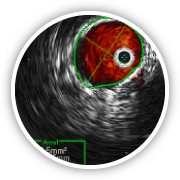

COMPLEX VENOUS

SURGERY & IVUS

Treatment, assessment with intravascular ultrasound (IVUS), management of complex deep venous thrombosis (DVT) and its complications including post thrombotic syndrome and chronic swelling